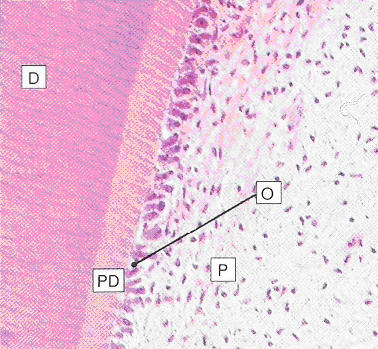

| Fig. 10.8 |

Stevens and Lowe p.147 |